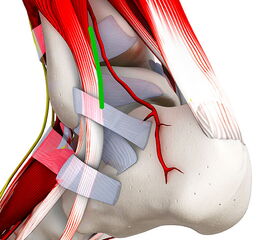

Abbildung 2: K-Draht Spreizer. Dieser erlaubt eine Distraktion des Gelenks über 1,8 mm Kirschnerdrähte. Diese Technik hilft in nahezu allen Fällen eine Innenknöchelosteotomie zu vermeiden.

Abbildung 2

• Spreizer mit Bohrungen für Kirschnerdrähte (Abbildung 2).